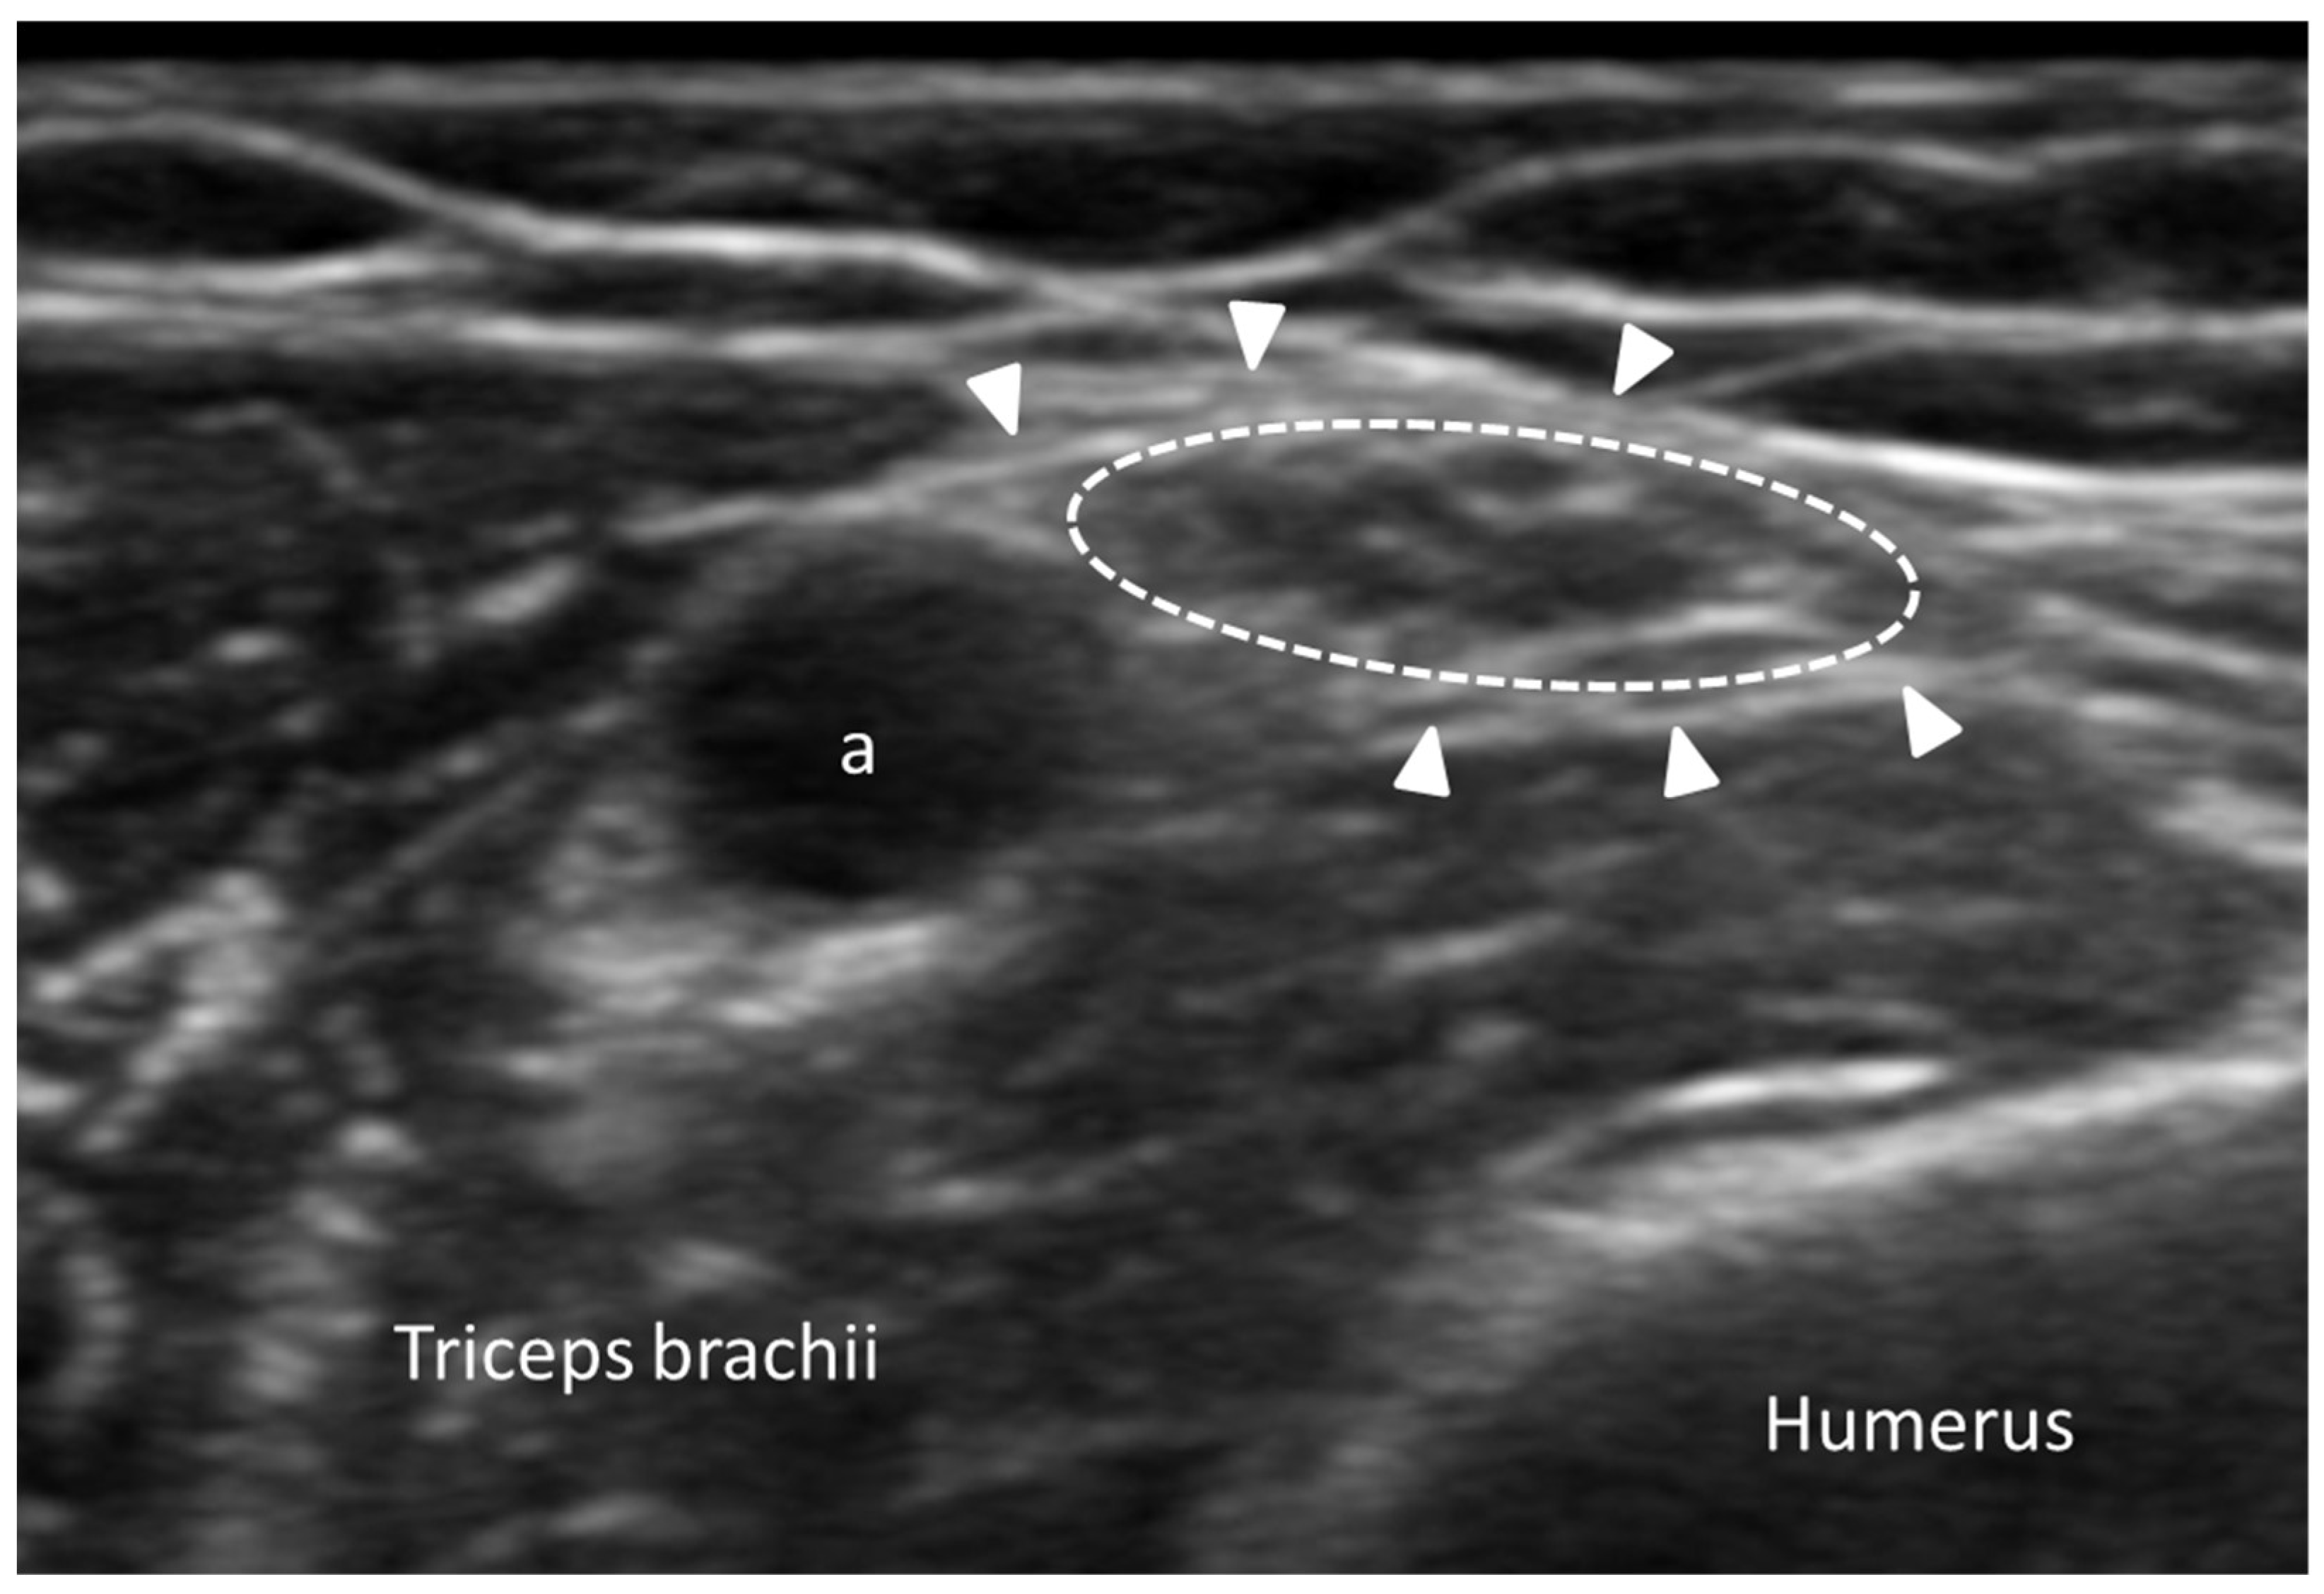

3.4.1. Nodular Fasciitis

- Yen, H.H.; Chiou, H.J.; Chou, Y.H.; Chen, C.H.; Guo, W.Y. Nodular Fasciitis: Sonographic-Pathologic Correlation. Ultrasound Med. Biol. 2017, 43, 860–867. [Google Scholar] [CrossRef] [PubMed]

- Lee, K.J.; Jin, W.; Kim, G.Y.; Rhee, S.J.; Park, S.Y.; Park, J.S.; Ryu, K.N. Sonographic Features of Superficial-Type Nodular Fasciitis in the Musculoskeletal System. J. Ultrasound Med. 2015, 34, 1465–1471. [Google Scholar] [CrossRef] [PubMed]

- Khuu, A.; Yablon, C.M.; Jacobson, J.A.; Inyang, A.; Lucas, D.R.; Biermann, J.S. Nodular fasciitis: Characteristic imaging features on sonography and magnetic resonance imaging. J. Ultrasound Med. 2014, 33, 565–573. [Google Scholar] [CrossRef] [PubMed]